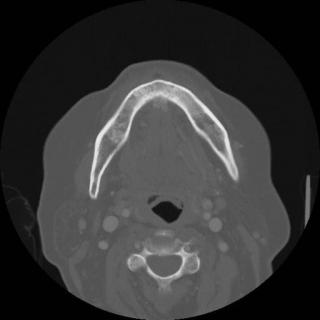

(Слева) При аксиальной КТ в костном окне у пациента, получавшего лучевую терапию по поводу плоскоклеточного рака носовой перегородки, визуализируется очаг литического характера в передних отделах верхней челюсти, представляющий собой треугольный участок деструкции костной ткани.

(Справа) При аксиальной КТ в костном окне у другого пациента определяются признаки выполненной резекции неба справа, а также изменения смешанного (склеротического и литического) характера в верхней челюсти слева, которая подвергалась облучению. Верхняя челюсть является относительно устойчивой к ионизирующему излучению, в ней редко возникает остеорадионекроз. Лучевые признаки идентичны таковым при поражении других костей лицевого скелета и основания черепа.

(Слева) При аксиальной КТ в костном окне визуализируется очаг литического характера с нарушением целостности кортикальной пластинки нижней челюсти слева. Возле корней моляров нижней челюсти слева определяются участки «просветления». Изменения (незаживающая язва, обнажение кости, а также факт использования бисфосфонатов) позволяют сделать заключение об остеонекрозе.

(Справа) При аксиальной КТ в костном окне определяются типичные признаки остеонекроза нижней челюсти, обусловленного внутривенным введением бисфосфонатов. Обратите внимание на очаг смешанного (склеротического и литического характера) в теле нижней челюсти слева в месте недавней экстракции зуба.